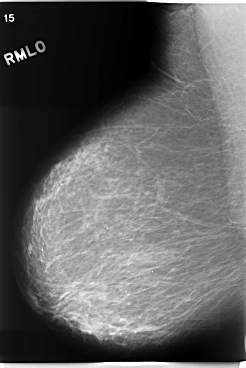

C_0205_1.RIGHT_MLO

RIGHT_MLO LINES 5880 PIXELS_PER_LINE 3936 BITS_PER_PIXEL 12 RESOLUTION 50 NON_OVERLAY